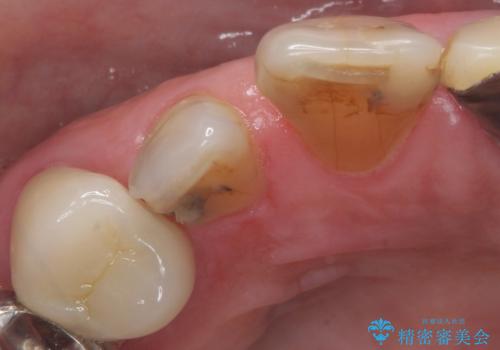

大きい虫歯で欠けた前歯 セラミッククラウンで治療

- 前歯が欠けたとのことで来院。

確認すると上の前歯の裏側に大きな虫歯がありました。

元々歯と歯の間のすき間が大きく食べ物が良く詰まるとのことでした。